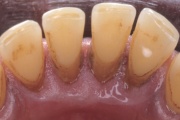

Krooniline parodontiit

Krooniline parodontiit on mikroobide poolt põhjustatud hammaste tugikudede põletik, mille tulemusena tekib progresseeruv alveolaarluu (nähtav röntgenograamil) ja periodontaalligamendi destruktsioon, igemetaskute moodustumine, igeme retsessioon või mõlemad kahjustused kombineeritult. Loe edasi »

- igemed veritsevad (19)

- igemed punetavad (21)

- igemed on tursunud/vohavad (17)

- igemepiir on taandunud (3)